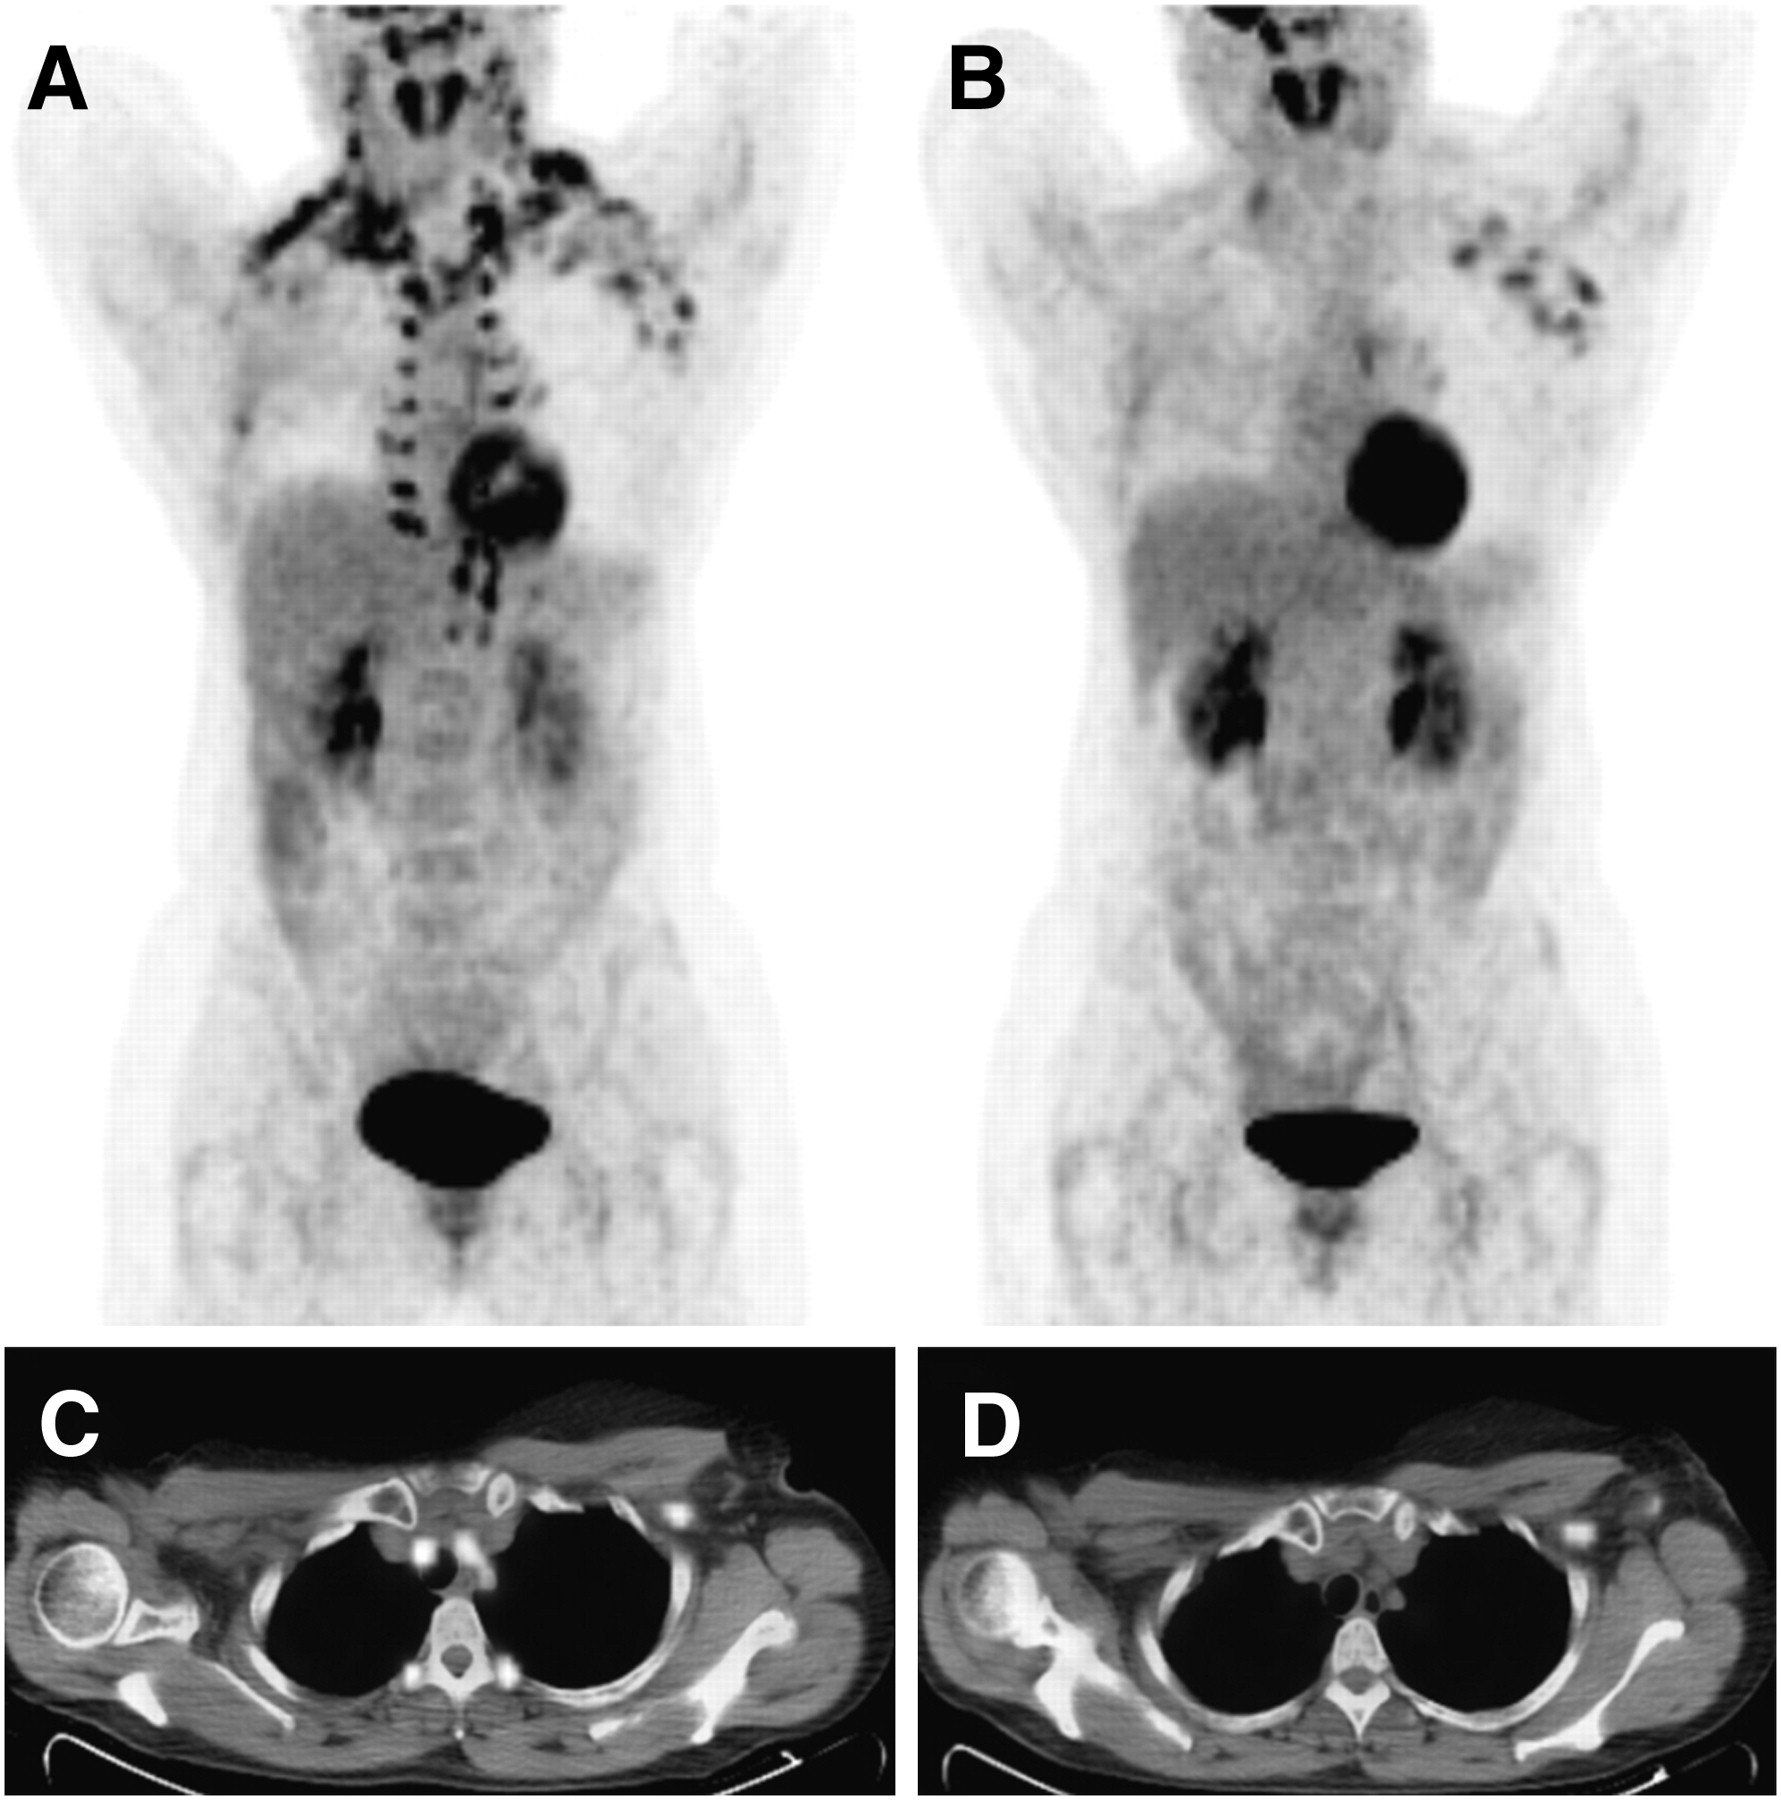

PSMA is een stof die na toediening via een infuus snel wordt opgenomen door de meeste soorten prostaatkanker en slechts weinig wordt opgenomen door de meeste andere organen in het lichaam. Bij de PSMA PET/CT wordt aan het PSMA een licht radioactieve stof (meestal Gallium-68 of Fluor-18) gekoppeld die straling afgeeft waardoor de prostaatkanker en de uitzaaiingen

op de scan zichtbaar worden.

PSMA therapie

Als aan het PSMA een agressievere radioactieve stof

wordt gekoppeld (meestal Lutetium-177) kunnen de tumoren niet alleen zichtbaar worden gemaakt maar ook lokaal worden bestraald.